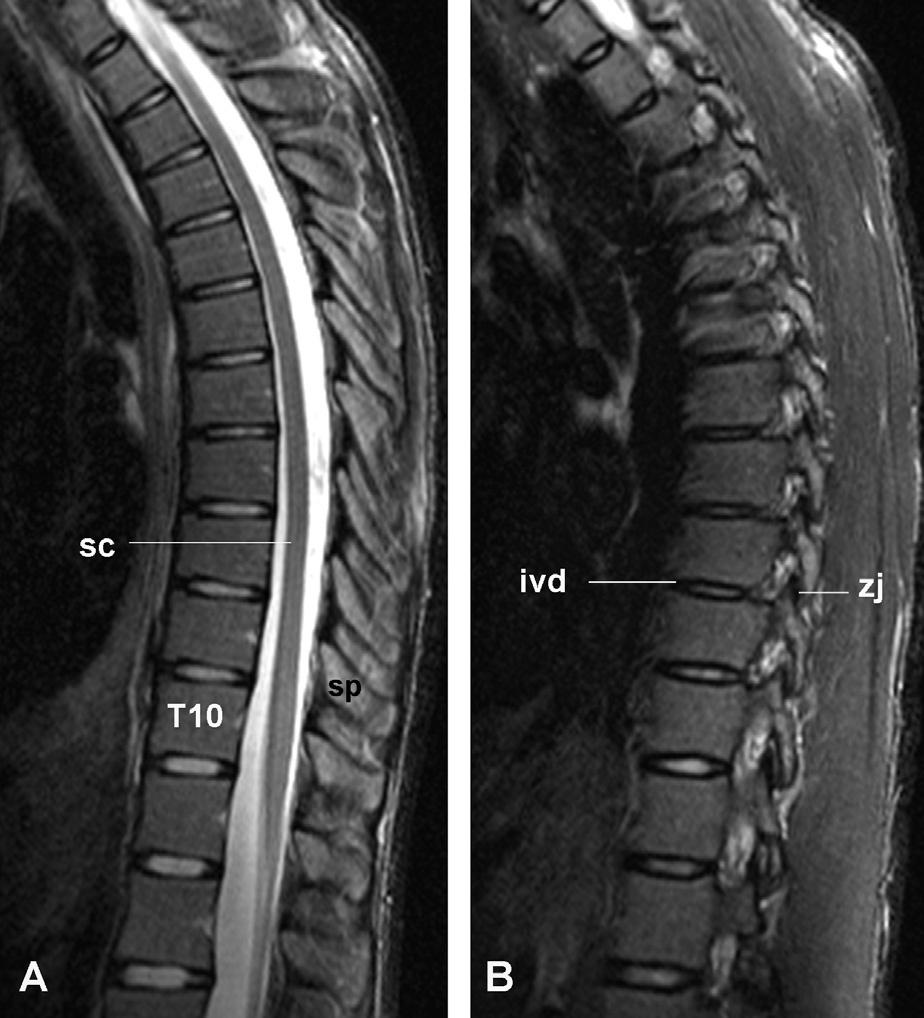

Fig.32.14. Sagittalmagneticresonanceimagesofthethoracic spine.(A)Mediansection,throughthevertebralbodies,spinal cord(sc),andspinousprocesses(sp)cord.(B)Paramediansectionthroughthezygapophysialjoints(zj).Intervertebraldiscs (ivd)areevidenceinbothsections.(CourtesyofDr.TimMaus, MayoClinic,RochesterMN.)